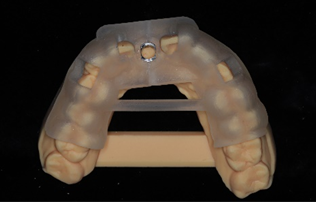

3. After disinfection, perform an intraoral trial fit of the guide to check if the pre-set window areas of the guide fit well with the teeth or other tissues. If not, adjust the obstructing areas and rinse for a trial fit. If it still does not fit well after adjustment, a new surgical guide needs to be made.

(Images provided by Dr. Zhu Xiao, Associate Chief Physician of the Department of Prosthodontics, Wuhan University)